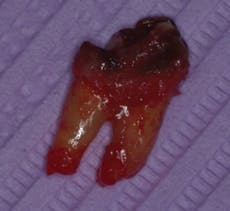

In the example shown in the photos, a patient presented with a severely broken down maxillary right first premolar tooth (No. 5) (Figure 2). Utilizing the Physics Forceps (Golden Dental Solutions), we atraumatically extracted the bifurcated remainder of this tooth (Figure 3) and curetted the socket. Once cleaned, bone grafting material (Foundation, J. Morita or Bioplant, Kerr Dental) was placed into the socket and sutured (Figure 4) to prevent any dislodgement.

Fig. 3 — Atraumatic extraction of tooth (4150)